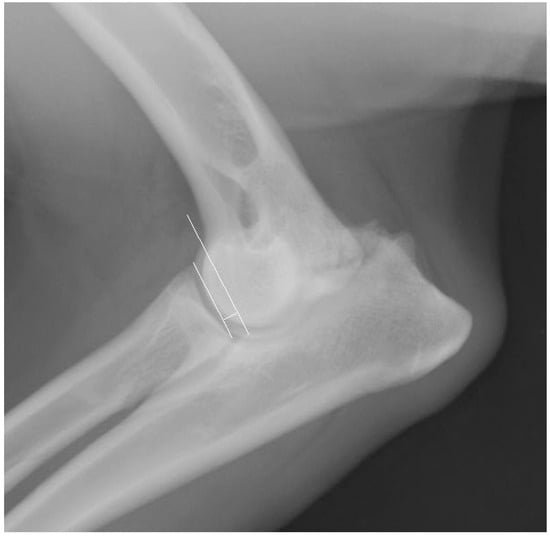

Is a Bacteriophage Approach for Musculoskeletal Infection Management an Alternative to Conventional Therapy? -